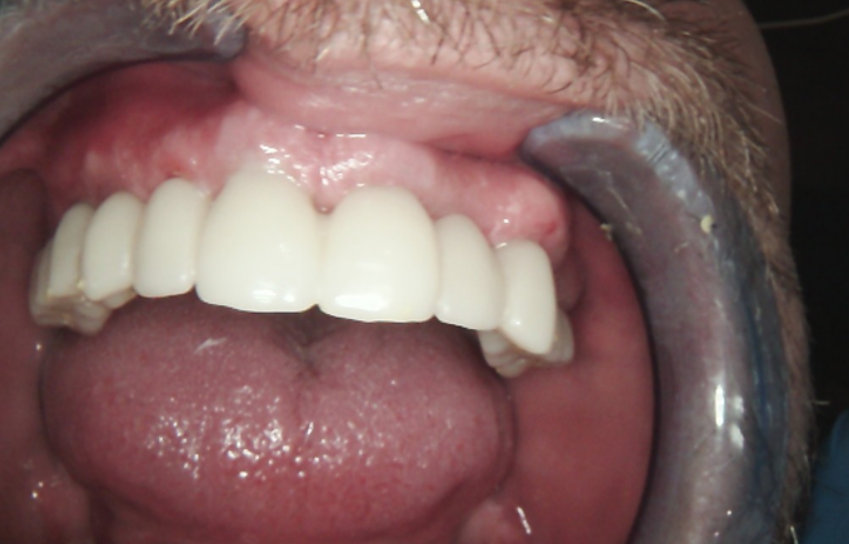

Currently, the patient is wearing the provisional PMMA prosthesis. He is attending regular professional hygiene appointments and adhering to a strict home care regimen. This transitional period allows for the evaluation of the function and esthetics of the PMMA prosthesis, so that any necessary adjustments can be made before fabricating the final restoration, ensuring an optimal outcome.

The patient’s appearance at this stage demonstrates a natural and harmonious result.